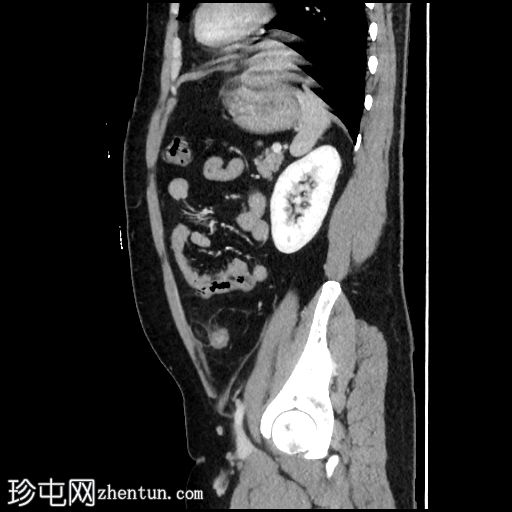

3.jpg

冠状位增强扫描(门静脉期)

乙状结肠和远端降结肠可见轻度环周壁增厚

结肠周围可见卵圆形脂肪密度病变,周围环绕软组织密度环,并可见脂肪条索状改变,符合大网膜垂炎的典型表现

未见憩室炎证据